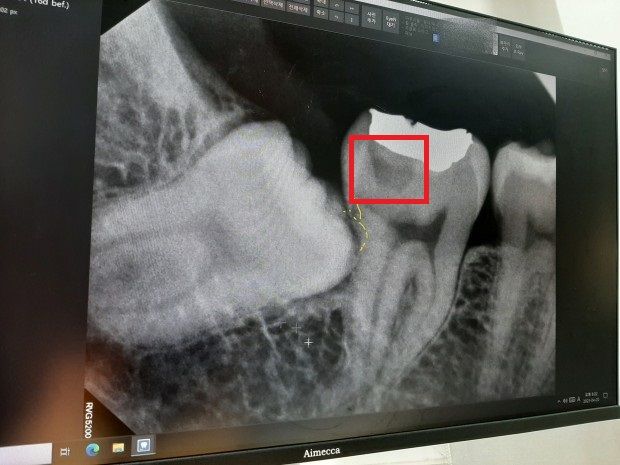

발치 전 사랑니 사진입니다.

1. 어금니 중간쯤에 푹 파인 부위가 충치가 있는 부위라고 설명해주시던데 현대의학으로는 치료는 어려우며 경과를 지켜보는 수 밖에 없다고 하셨는데 그럼 몇개월마다 사진을 찍어봐야 할까요?

3. 어금니 골드 인레이 보철한 아래 부분에 어두운 색이 있는데 이게 충치 의심된다는데 사진 상으로도 충치가 맞을까요? (빨간색 네모로 체크한 부분입니다.)

사실 저 부위는 새로 골드 인레이한지 4년~5년 정도 밖에 안되었거든요. 현재 다른 쪽의 금니는 15년 넘게 써도 멀쩡한데 새로한지 얼마 안된 부위가 충치 의심된다고 하니 정말 그런가 싶어서요.